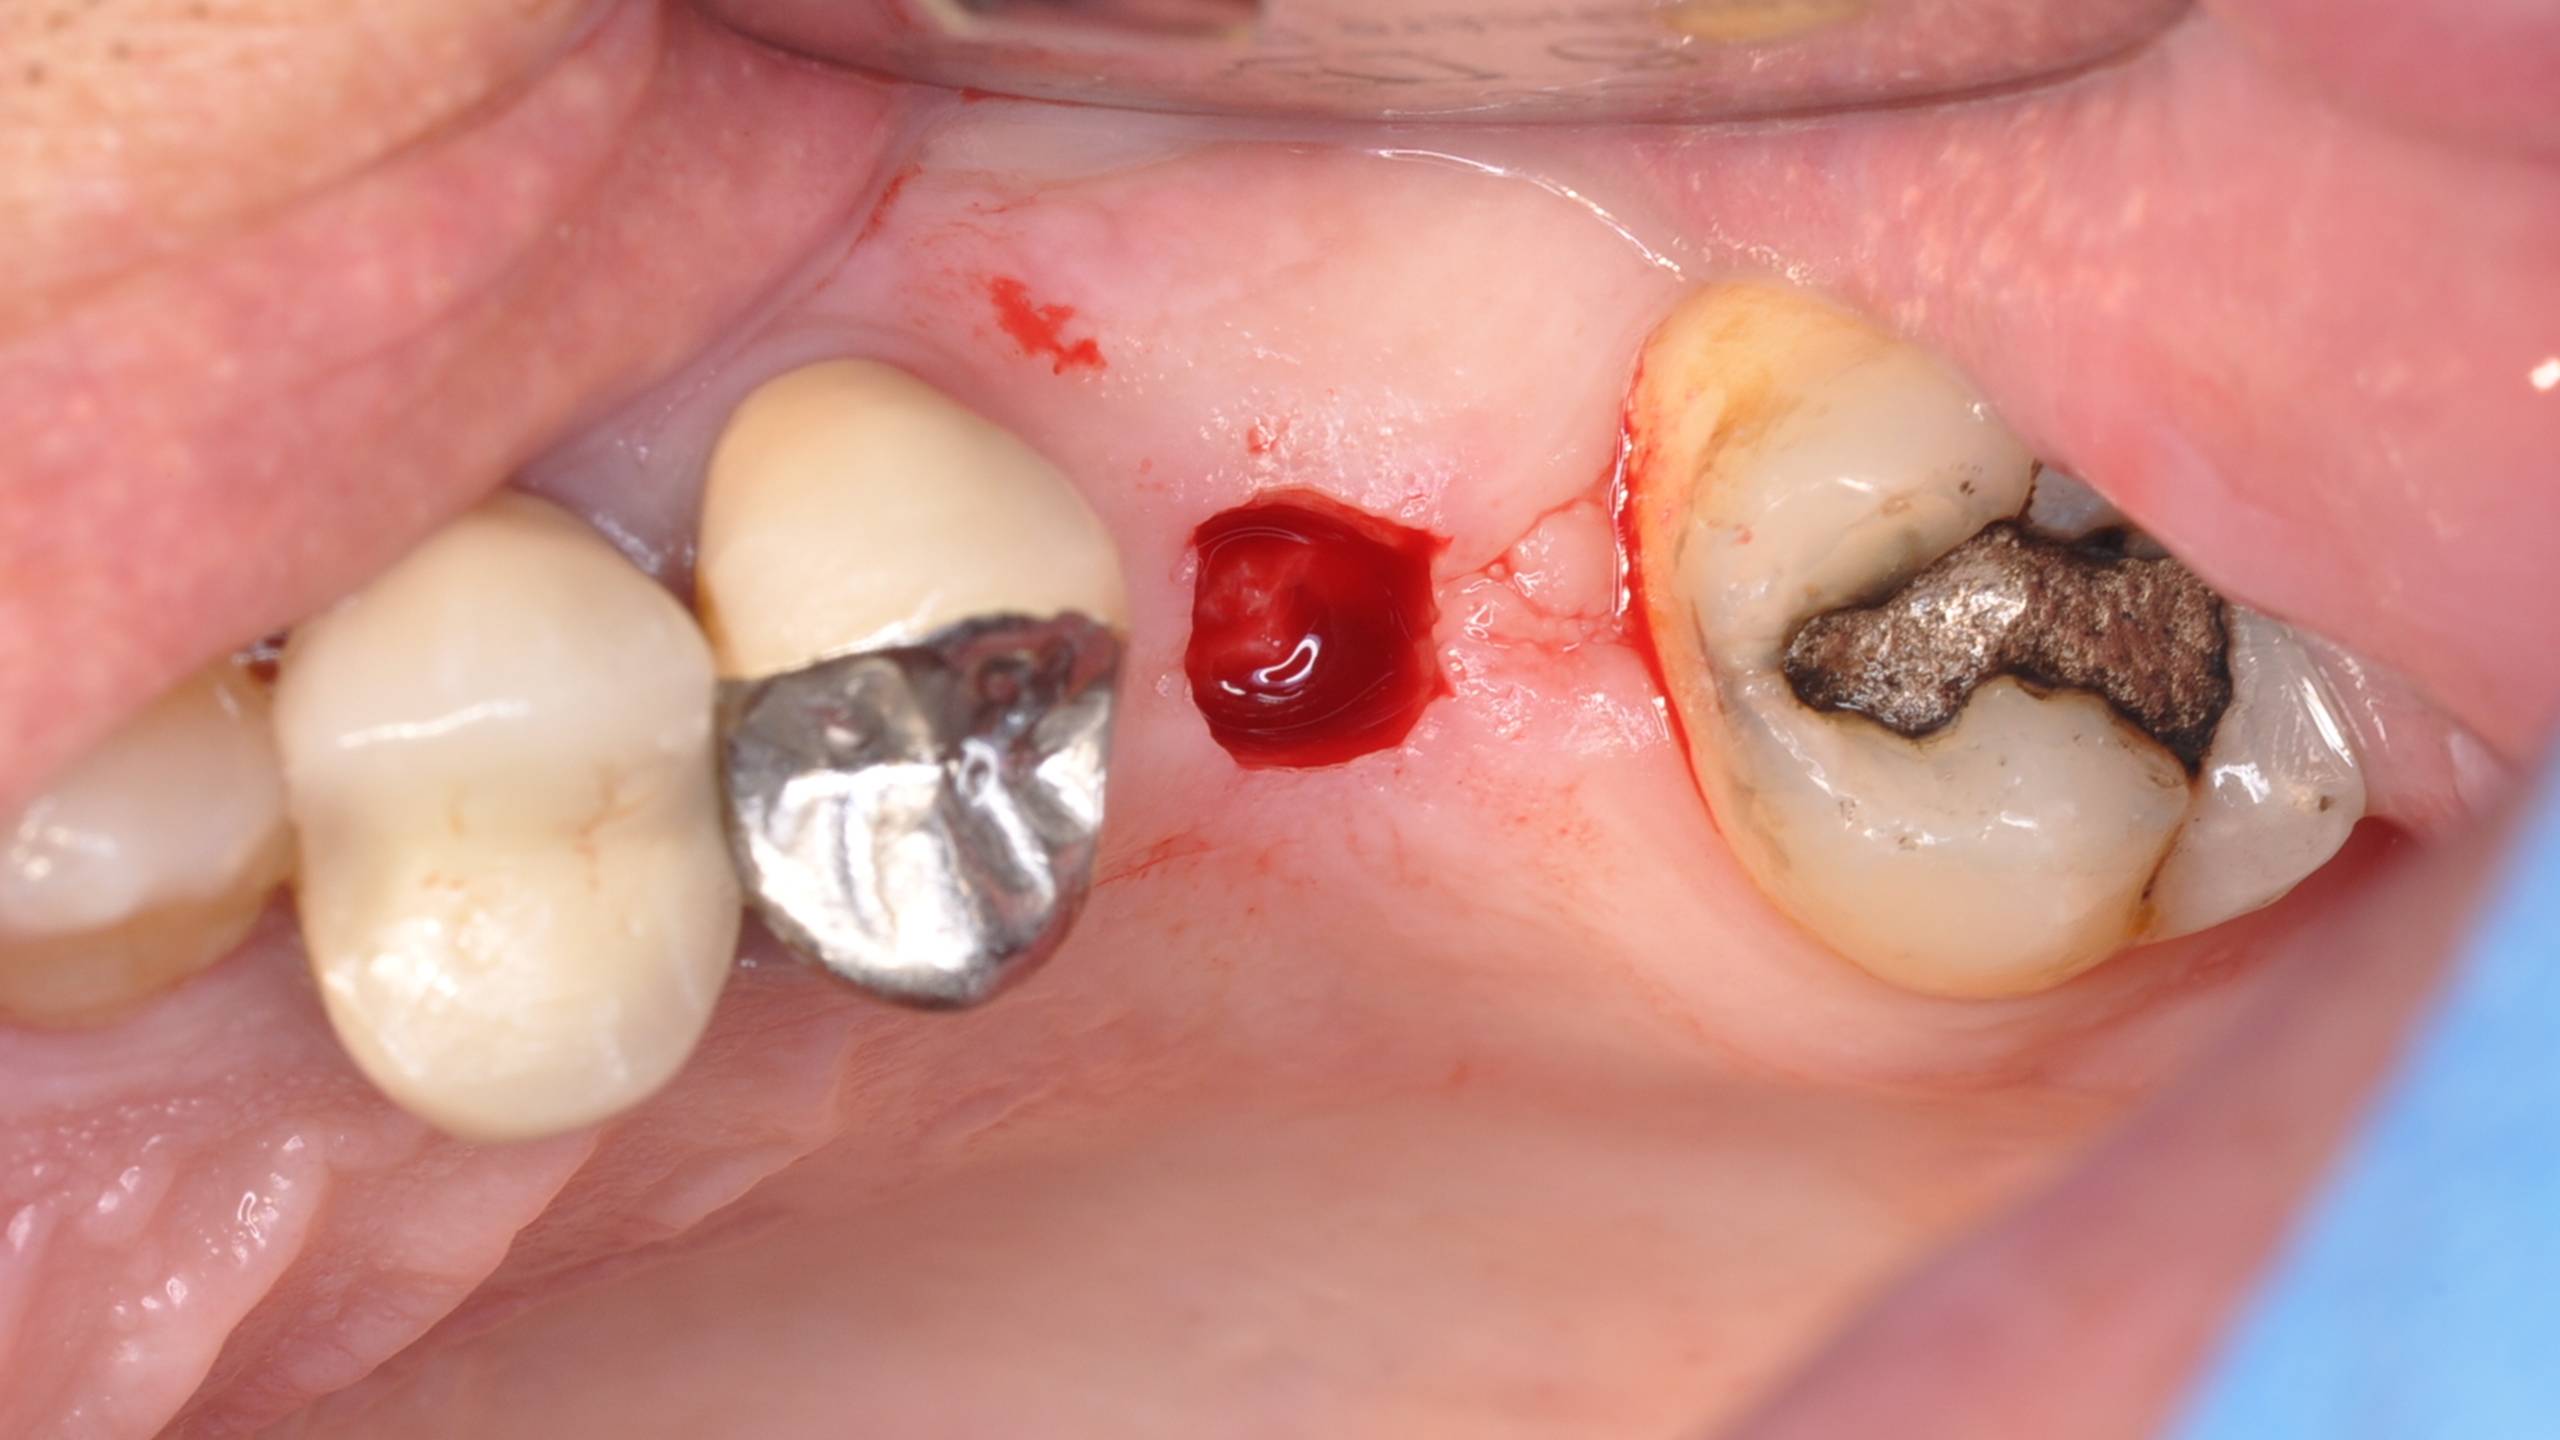

Cas d’une patiente présentant une absence de 26.

Réalisation d’une gingivectomie permettant un abord crestal dans le but de la pose d’un implant en flapless.

Utilisation d’un osteotome afin de fracturer le plancher sinusien, puis apport d’un matériau de comblement synthétique ( Easygraft SUNSTAR) per opératoire.

Visualisation du matériau avant qu’il ne soit refoulé dans le sinus.